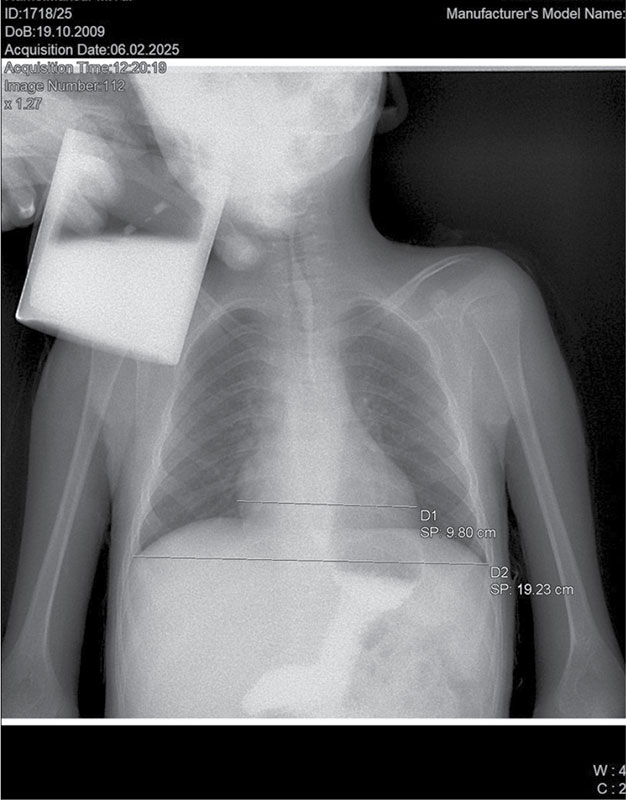

Рис. 1. Рентгенологическое исследование органов грудной клетки. Сердечно-грудной индекс – 0,58 (горизонтальный размер тени сердца – 9,98 см)

Рентген органов грудной клетки: отмечается повышенный горизонтальный размер тени сердца – 9,98 см. Сердечно-грудной индекс – 0,58 – повышен и характерен для начальной стадии дилатационной кардиомиопатии (рис. 1).

Рентген органов грудной клетки: отмечается повышенный горизонтальный размер тени сердца, однако в динамике отмечается снижение до 9,72 см. Сердечно-грудной индекс также снизился до 0,57 (рис. 2).